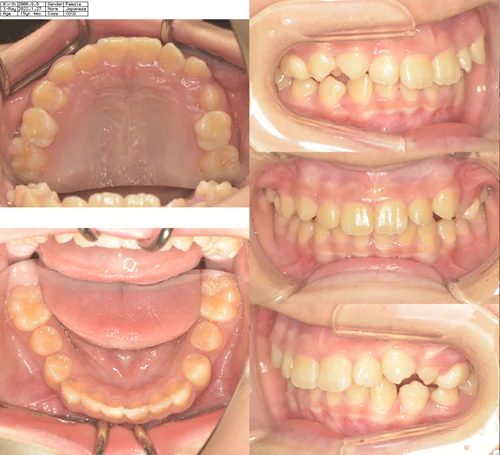

症例

case.1

治療前 治療中 治療後

治療開始の年齢 13歳3ヶ月

治療名 上顎両側3番埋伏歯開窓牽引

治療内容 叢生及び異所萌出歯の配列

費用 770,000円

治療期間 1年7カ月